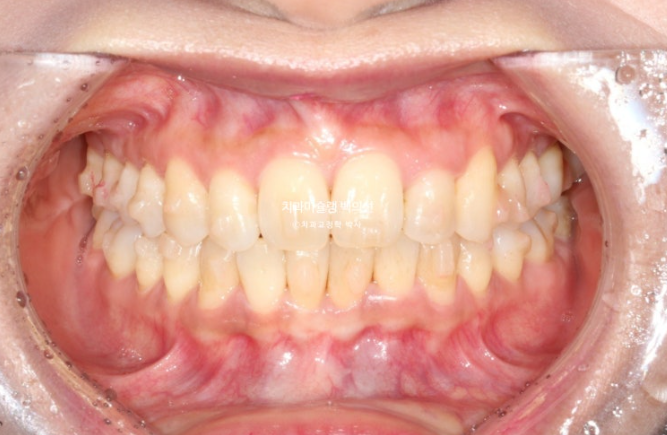

1년 전, 교정치료를 위해 온 환자분입니다.

환자분이 고치고 싶은 것은 덧니입니다.

송곳니와 작은어금니 덧니가 보이며 작은어금니가 거꾸로 물리는 반대교합도 보입니다.

앞니 중심선은 약 2mm 어긋나 있습니다.

위 앞니가 아래앞니를 많이 덮어 깊게 물리는 과개교합도 있습니다.

덧니로 배열에서 튀어나와있는 치아들은 잇몸이 내려가 있습니다.

다행히 큰어금니 교합은 좋은 편